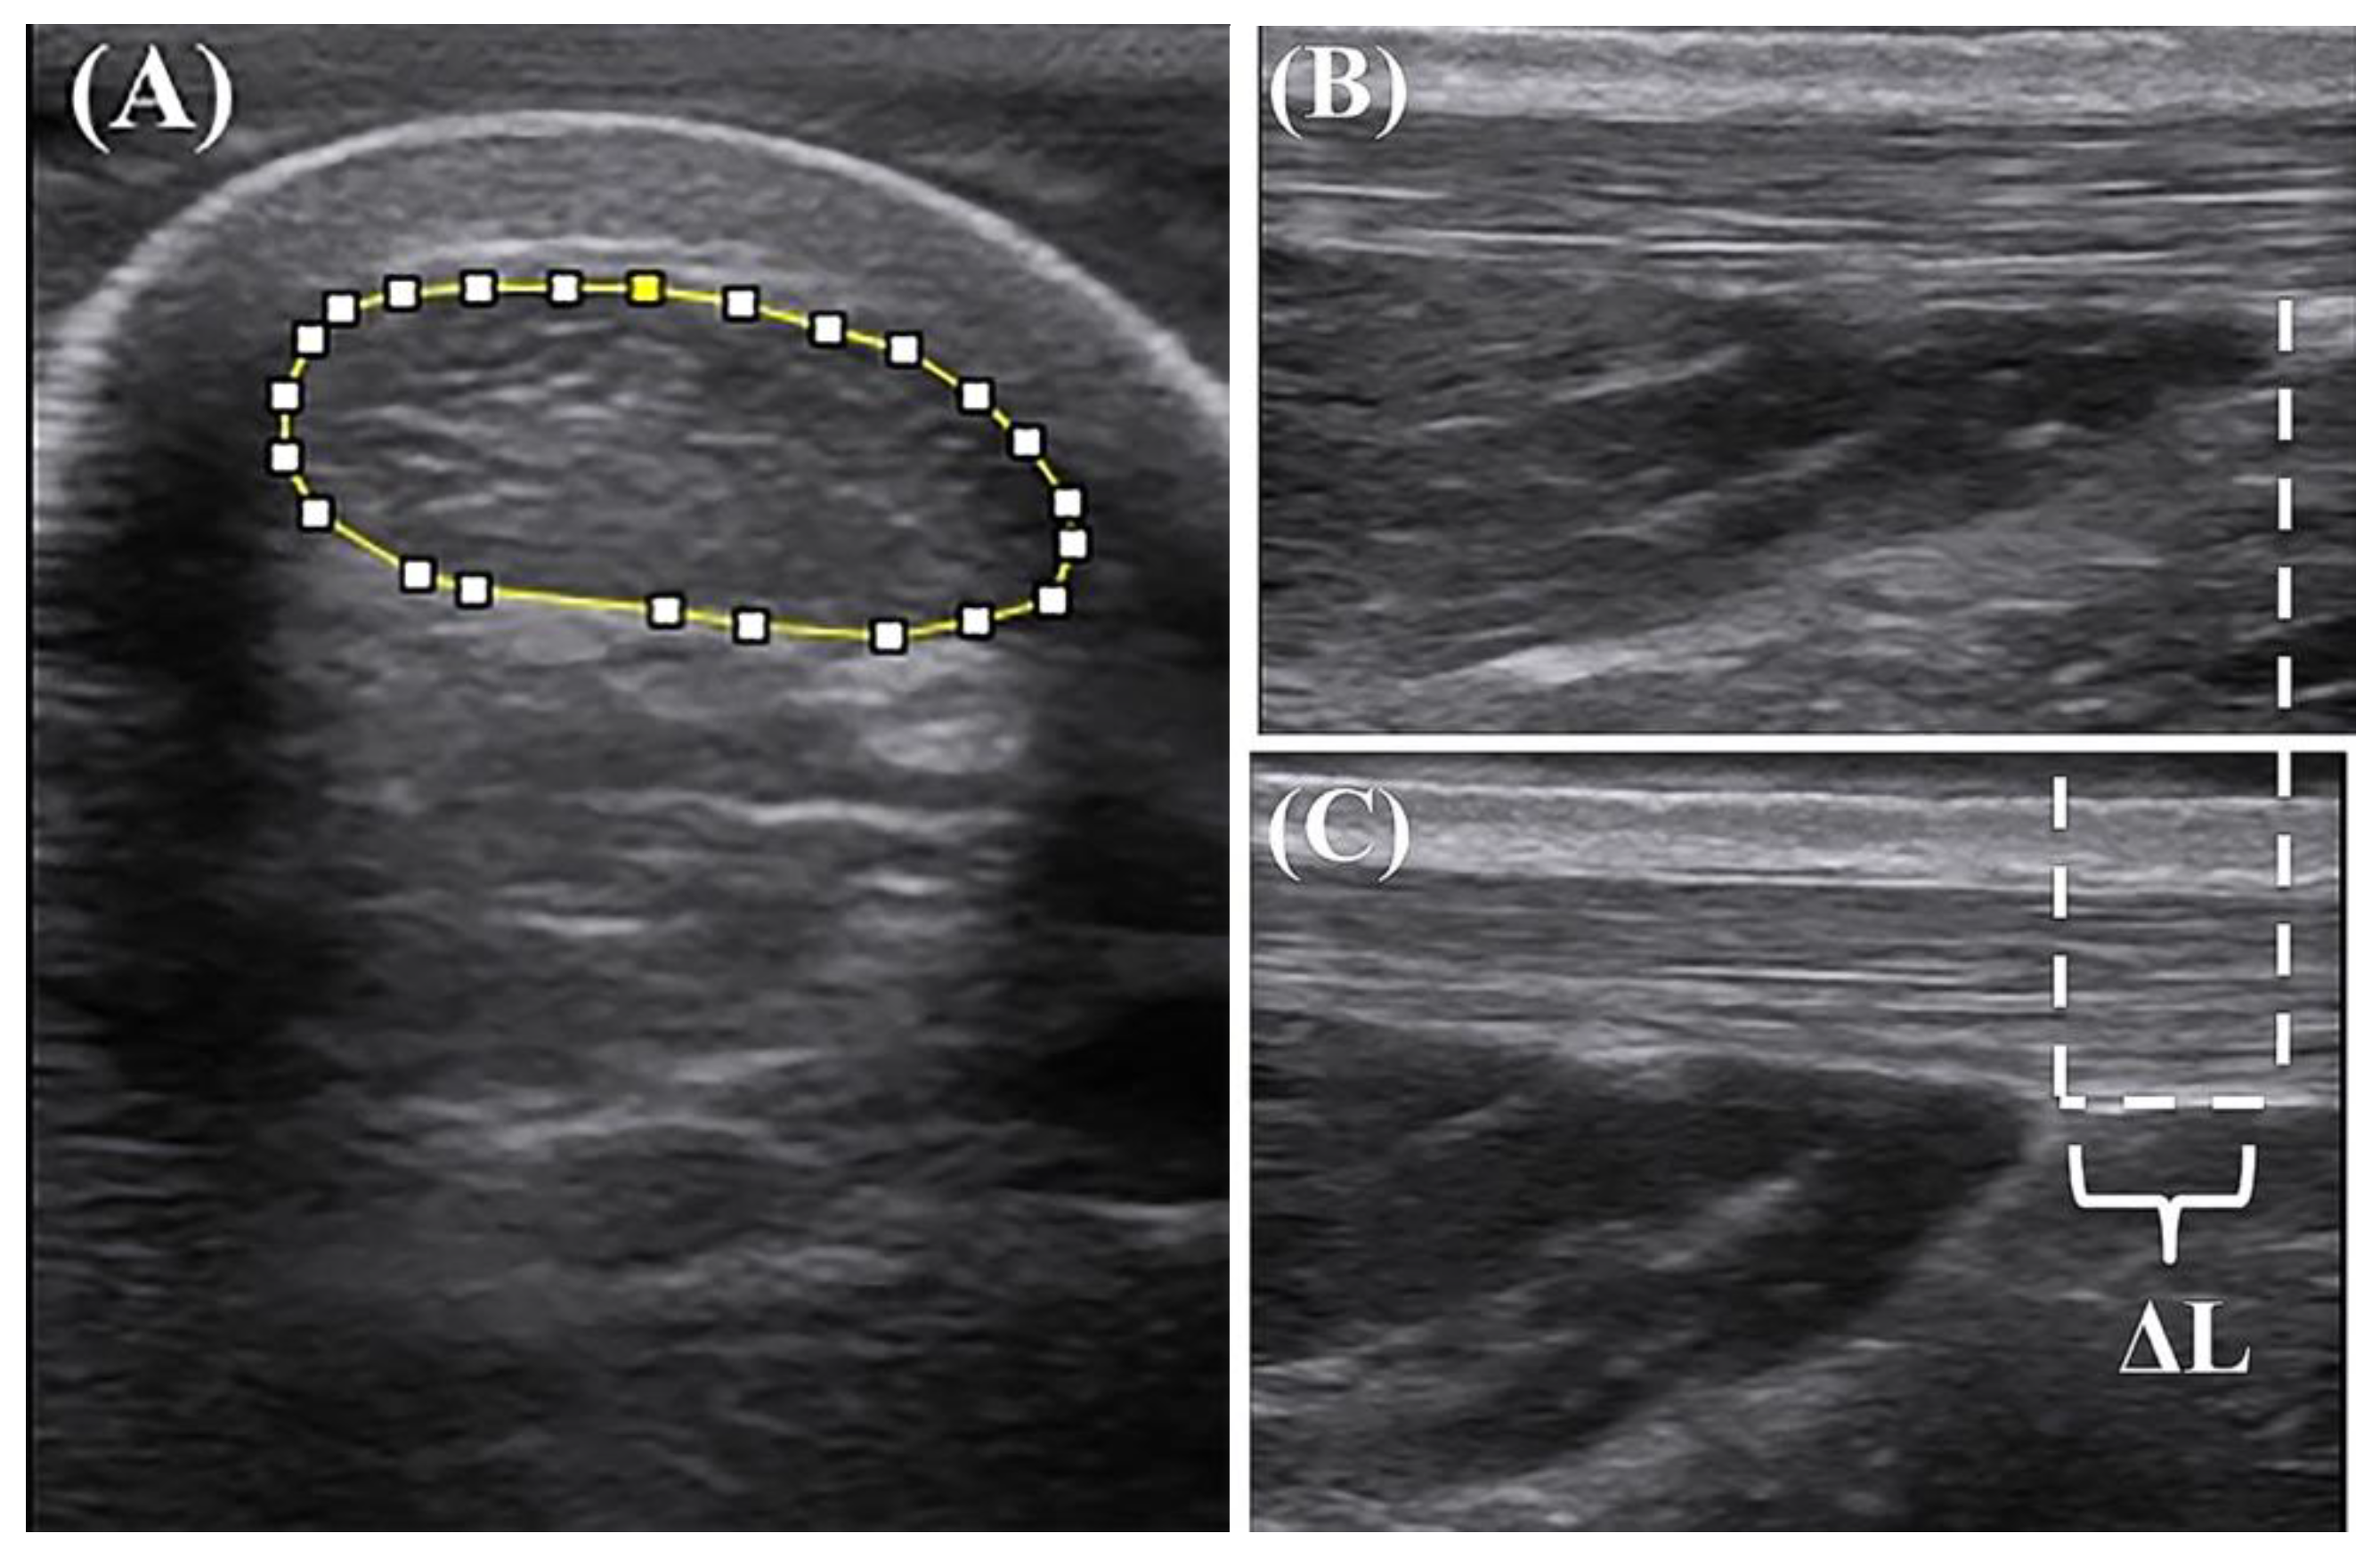

3.2. AT Morphology

3.3. AT Mechanical Properties